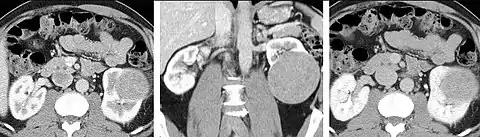

Detection and characterization of renal parenchymal masses is a frequent indication for CT. An initial noncontrast CT is important for detecting calcium or fat in a lesion, and to provide baseline attenuation of any renal masses. Following noncontrast scanning, intravenous contrast is injected and a corticomedullary phase is obtained at approximately 70 seconds (figure 7a, 7b). The corticomedullary phase is characterized by enhancement of the renal cortex as well as the renal vasculature. This phase is valuable in the evaluation of benign renal variants, lymphadenopathy and vasculature, however certain medullary renal masses may not be visible during this phase due to minimal enhancement of the medulla and collecting system. The parenchymal phase is obtained approximately 100-200 seconds after the injection of contrast material (figure 7c). Parenchymal phase imaging demonstrates continued enhancement of the cortex, enhancement of the medulla, and various levels of contrast material in the collecting system. The parenchymal phase is highly important for the detection and characterization of renal masses, parenchymal abnormalities, and the renal collecting system. This method of imaging does not evaluate for abnormalities of the collecting system.

Common renal masses can occasionally be differentiated from each other using this imaging technique. Renal cell carcinomas and oncocytomas typically demonstrate intense heterogeneous enhancement on the parenchymal phase images and cannot be reliably differentiated from each other but can be distinguished from other renal masses. Angiomyolipomas (AML’s) also demonstrate intense contrast enhancement but characteristically contain macroscopic fat which can be detected on the noncontrast images, and can help to differentiate AML’s from renal cell carcinomas and oncocytomas. Renal lymphoma on the other hand, will often have decreased enhancement when compared to the renal parenchyma on the parenchymal phase images.

FIGURE 7. Selected images from a renal mass specific protocol CT. Corticomedullary phase (axial 7a) demonstrates peripheral enhancement of the renal cortex with minimal opacification of the renal medulla. There is a large renal cell carcinoma in the left kidney (right in image) which can be differentiated from the normal renal parenchyma by the heterogeneous and differential enhancement. The renal artery and vein are opacified in this phase as well. The collecting system is not opacified (coronal reformat 7b). In the parenchymal phase, the renal cortex and the medulla are enhancing. The renal cell carcinoma in the left kidney is not as well defined when compared to the corticomedullary phase images, but is actually slightly more conspicuous. There is some contrast noted within the collecting system during this phase (7c).